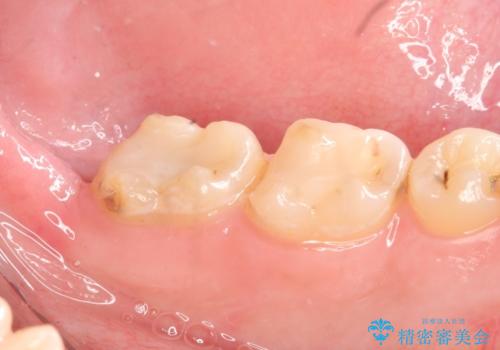

- 左下奥歯がしみるといらっしゃった方の症例です。

左下7の虫歯は深く、また歯冠高径も低かったため、歯冠長延長術を行いました。